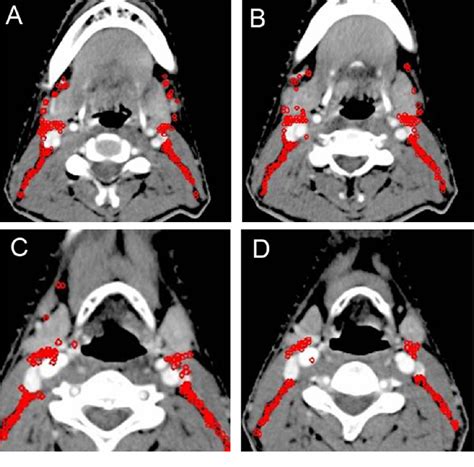

• Imaging Studies: Imaging tests such as X-rays, CT scans, or MRIs may be used to visualize the lymph nodes and surrounding tissues.